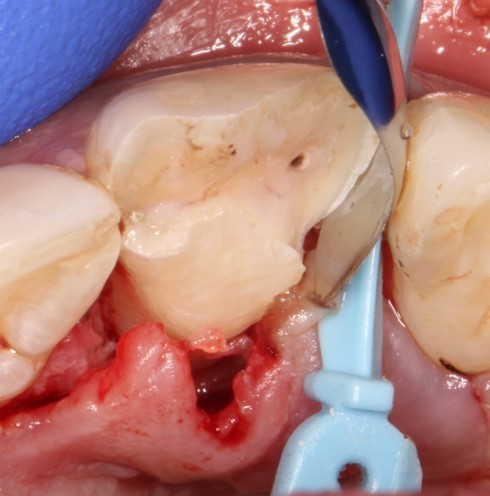

Лечение: Под местной анестезией убрали часть сколотого зуба

Отслоили мягкие ткани (а)

Редуцировали часть костной пластинки (б)

На данной фотографии продемонстрирована припасовка осколка зуба. Далее зуб и осколок был вычищен и адгезивно подготовлен к фиксации.